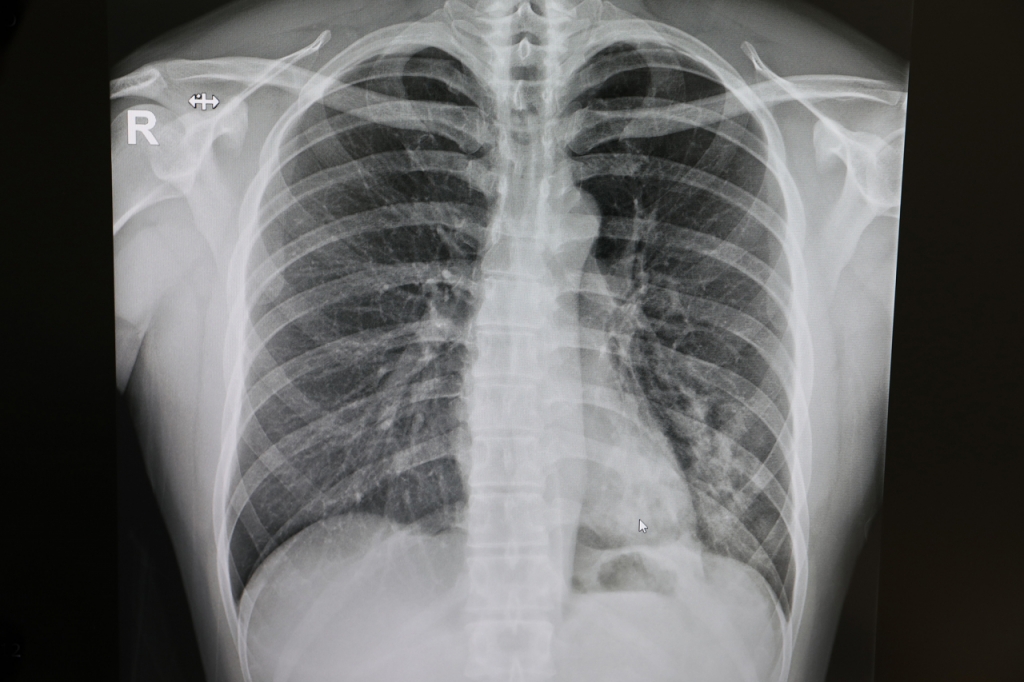

마이코플라즈마에 감염되면 기침, 거친 숨소리(천명), 발열, 인후통 등의 증상이 나타난다. 초기에는 감기 증상과 비슷하지만, 기침과 열이 심해지는 경향을 보인다.

마이코플라즈마균은 주요 폐렴 원인균으로, 감염환자의 10~15%에서 중증 폐렴이 생길 수 있어 조기 치료가 중요하다. 특히 소아는 마이코플라즈마 감염을 앓는 중이라도 다른 바이러스에 동시 감염이 생길 위험이 높아 부모들은 위생 관리 및 감염자 접촉을 줄이는 등 예방조치와 조기 치료가 필요하다.